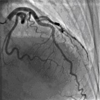

Compared with medical therapy alone, coronary artery bypass grafting (CABG) significantly reduced cardiovascular deaths and the composite end point of all-cause deaths and cardiovascular-related hospitalizations, reported investigators from the Surgical Treatment of Ischemic Heart Failure (STICH) trial. However, the effect of the two management strategies on overall survival in patients with ischemic heart failure was similar.